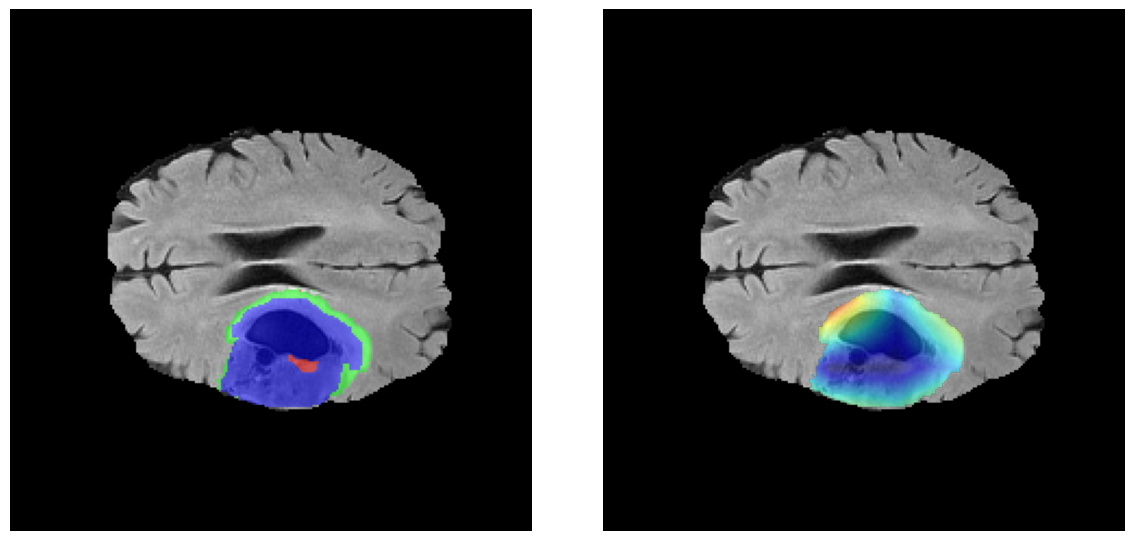

Mapas de Explicabilidad (Grad-CAM++)

Visualización de las regiones de atención del modelo que validan su razonamiento clínicamente relevante

Ejemplos LGG - Atención Difusa en Edema Peritumoral

LGG Grad-CAM++ 1 LGG Grad-CAM++ 2 LGG Grad-CAM++ 3 LGG Grad-CAM++ 4 LGG Grad-CAM++ 5 LGG Grad-CAM++ 6

Para casos LGG, la atención del modelo es más difusa y se concentra principalmente en la región de Edema Peritumoral (verde), consistente con la naturaleza más infiltrativa y menos agresiva de estos tumores.

El análisis Grad-CAM++ reveló que el modelo desarrolla automáticamente la capacidad de localizar las regiones tumorales. Para casos HGG, la atención se alinea fuertemente con las regiones de Tumor Realzado (ET) y Núcleo Necrótico (NCR). En contraste, los casos LGG muestran atención más difusa, principalmente concentrada en la región de Edema Peritumoral (ED), lo cual es consistente con la patofisiología conocida de los gliomas.